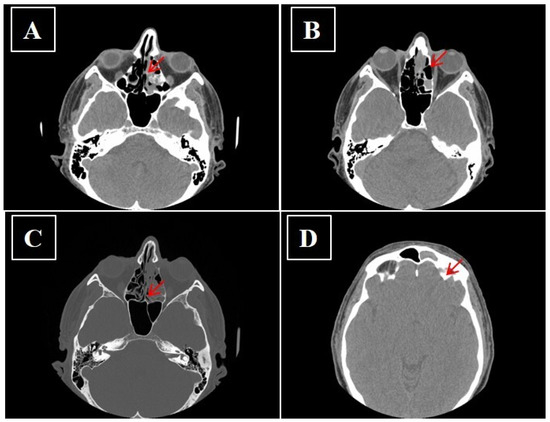

- Kawaguchi, M.; Kato, H.; Tomita, H.; Mizuta, K.; Aoki, M.; Hara, A.; Matsuo, M. Imaging Characteristics of Malignant Sinonasal Tumors. J. Clin. Med. 2017, 6, 116. [Google Scholar] [CrossRef]